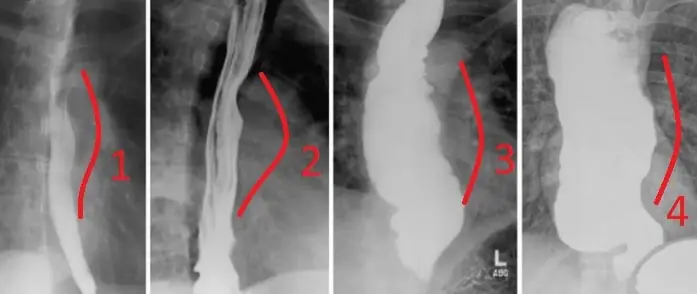

Dilatasyon, tıp dilinde genişleme anlamı taşımaktadır. Herhangi bir organın normal hacminin artması o organın dilatasyonu demektir. Dilate olmak, dilatasyona uğramak olarak ta geçmektedir. Kolayca kavrayabilmek adına aşağıdaki görseli dikkatlice inceleyiniz :

Görselde 1 ve 2 numaralı işaretlenen yerler normal damarı temsil ederken 3 numaralı yer ise dilatasyona uğramış damarı temsil etmektedir. Çeşitli etkiler aracılığıyla ilgili yapının genişlemesi ya da olması gereken normal boyutunun artması dilatasyon nedir sorusunun en genel cevabıdır.